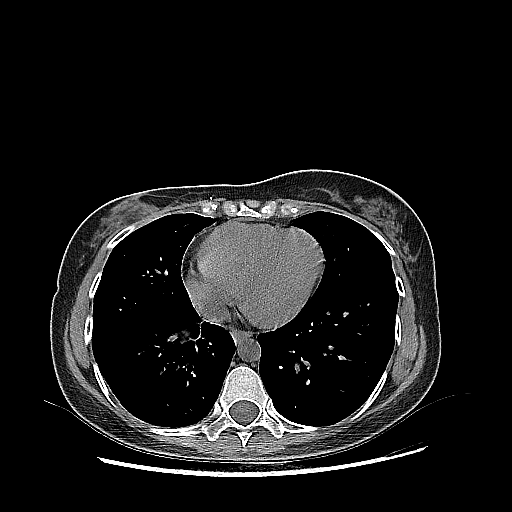

Image Grid

4Γ—3 grid: Rows show different image types (Original NATIVE, Reconstructed NATIVE, Original VENOUS, Generated VENOUS), Columns show windowing techniques (No Window, Lung Window, Mediastinum Window)

Original NATIVE CT scan (input)

Full window (WL 1023.5, WW 4095 β†’ Low βˆ’1024, High +3071)